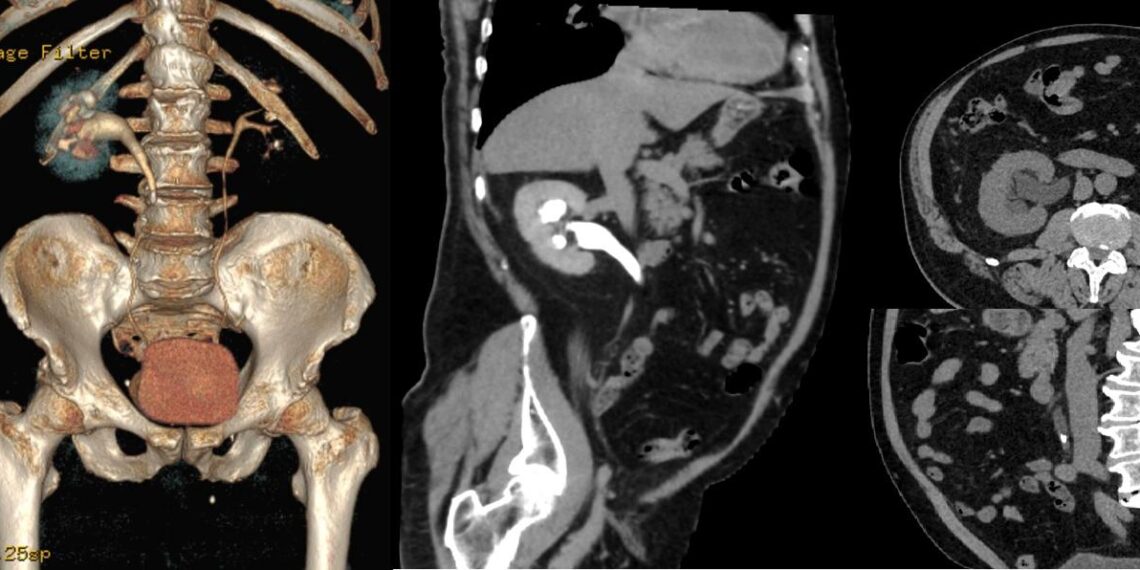

„URO-CT-ul este considerat o evaluare superioară față de urografia clasică, deoarece oferă imagini mai detaliate și poate detecta o gamă mai largă de afecțiuni. Investigația folosește o combinație de raze X pentru a genera imagini în secțiune ale rinichilor, ureterelor și vezicii urinare. Procedura este non invazivă, iar rezultatele se pot obține foarte repede, ceea ce permite începerea unui potențial tratament într-un interval de timp foarte scurt. Pentru a capta imagini și mai clare, se utilizează, de obicei, o substanță de contrast iodată, care este injectată în venă înaintea scanării”, spune asist. univ. Emil Stoicescu – Radiologie si imagistică medicală Spitalul de Boli Infecțioase și Pneumoftiziologie Dr. Victor Babeș Timișoara.

„Este important de menționat că, înainte de a efectua o tomografie computerizată urologică, se vor lua în considerare factorii individuali ai pacientului, inclusiv istoricul medical, simptomele, dar și alte investigații anterioare. Imaginile obținute prin URO-CT furnizează informații legate de extinderea și localizarea precisă a unei afecțiuni, ceea ce permite stabilirea unui plan terapeutic pentru fiecare pacient în parte. De exemplu, în cazul pietrelor la rinichi, dimensiunea și localizarea acestora pot influența decizia cu privire la intervenția chirurgicală sau la alte metode de tratament. De asemenea, cu ajutorul acestui screening poate fi apreciată si calculată densitatea calculului reno-urinar. Datorită capacității sale de a evidenția chiar și cele mai mici modificări ale țesuturilor și structurilor anatomice, URO-CT-ul poate contribui la detectarea precoce a afecțiunilor urologice”, spune asist. univ. Emil Stoicescu – Radiologie si imagistică medicală Spitalul de Boli Infecțioase și Pneumoftiziologie Dr. Victor Babeș Timișoara.